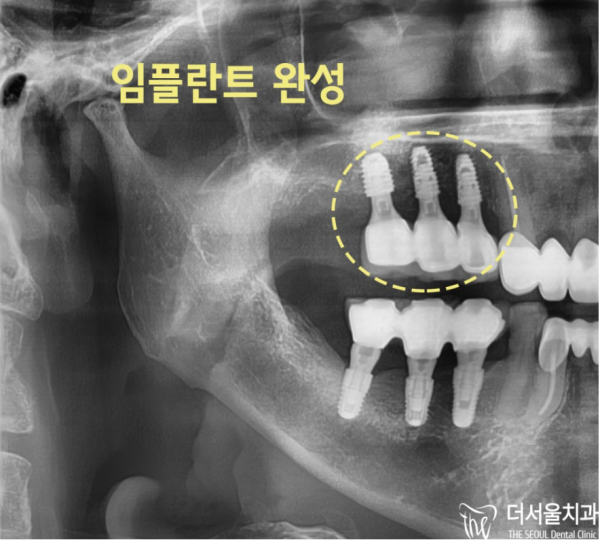

이 환자분은 14, 15번의 작은 어금니부터 픽스처를 식립하면서 16번 부위에 뼈이식을 하고

뼈이식이 잘 마무리되면 그때 16번 부위에 픽스쳐를 식립하기로 하였습니다.